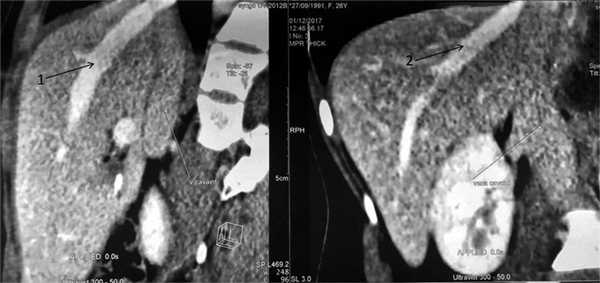

В венозную фазу левая ветвь воротной вены прослеживается в начальном сегменте, в области бифуркации, далее вовлечена в патологический процесс. Также выявлен фрагмент правой ветви воротной вены, плотно прилежащий к паразиту (рис. 4). Рис. 4. МСКТ-ангиограммы брюшной полости (венозная фаза). 1 — правая печеночная вена, 2 — срединная печеночная вена.

На МСК-томограмме грудной клетки справа в кардиодиафрагмальном углу, в переднем средостении, прилегая к грудной стенке и перикарду, определяется образование с включениями кальция, размером 42×32 мм (рис. 5). Рис. 5. МСКТ-ангиограмма грудной клетки и брюшной полости. Патологический очаг в левой доле печени (1) и кардиодиафрагмальном углу (2).